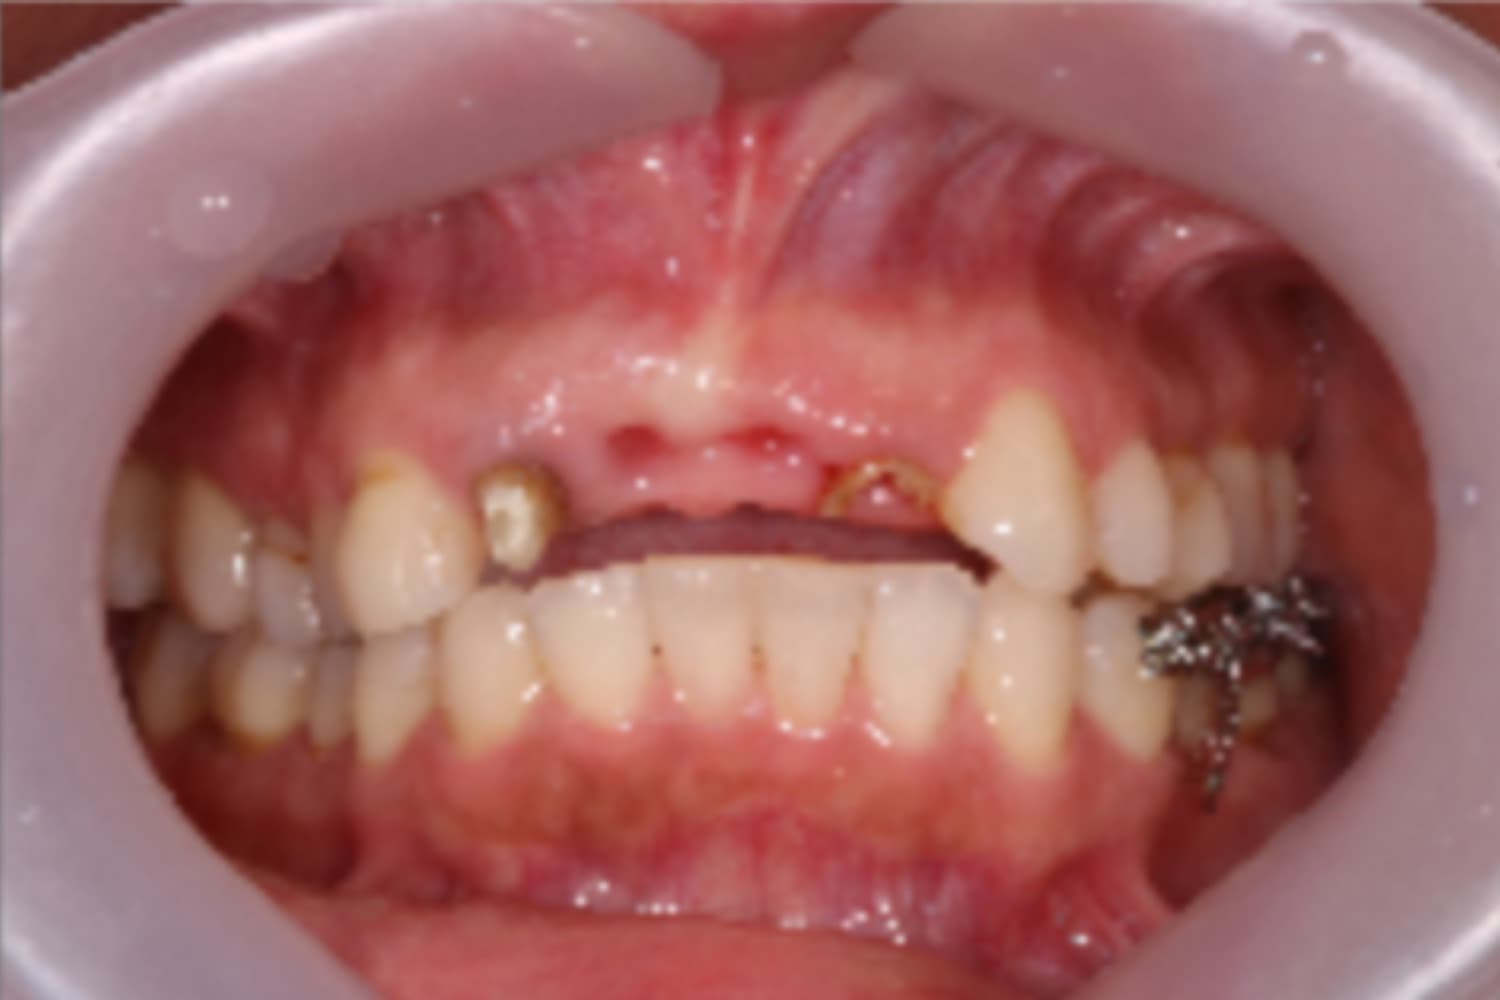

左上犬歯のインプラント治療

Before

After

抜歯と同時にインプラント治療を行いました。

主訴

左上犬歯の被せ物の脱離

治療期間

6カ月

治療回数

8回

費用

533,500円

副作用・リスク

・抜歯後即時にインプラントを埋入するため、結合不良リスクが高いです。 ・結合不良の場合、インプラント再埋入など追加処置が必要となります。